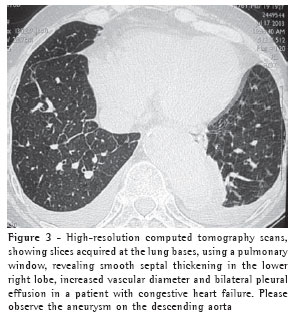

Overall, ground-glass opacities and thickening of the interlobular septa were the most common findings, occurring in 100% of the cases (Figures 1 and 2).

The thickening of the interlobular septa was bilateral in thirteen cases (Figures 1-4) and unilateral in two, also in the patients with fibrosing mediastinitis. In all cases, the thickening was of the smooth type.

All cases of interlobular septal thickening (100%) were accompanied by ground-glass opacities. Nevertheless, the mosaic pattern of attenuation was observed in only ten cases (66%) (Figure 1).

Pleural effusion was the third most common tomographic finding overall and was the most common nonparenchymal finding, being found in 13 patients (87%), predominantly in the bilateral form (n = 11) (Figures 1-3).

Ground-glass opacities were detected in all fifteen patients (100%) and were bilateral in thirteen. Ground-glass opacities were unilateral only in the two fibrosing mediastinitis patients. In another study,(9) ground-glass opacities were observed in six of seven patients with hydrostatic edema.

Thickening of the interlobular septa was a common finding accompanying hydrostatic edema, occurring in 100% of the patients and corresponding to the interstitial pathway for the drainage of excess pulmonary fluid. In thirteen patients (87%), the thickening was bilateral, whereas it was unilateral in two (13%). The interlobular septal thickening was smooth in all of the cases (100%). In another study(9) involving four patients, only one presented a nodular aspect, which was likely attributable to an increase in septal vein diameter. Nodular thickening of the interlobular septa is a common finding in a number of diseases, particularly in sarcoidosis and lymphangitic carcinomatosis.(16)

Septal thickening was not found in isolation. In all patients presenting septal thickening, there were also ground-glass opacities, and the mosaic pattern of attenuation was observed in ten patients (67%). In another study,(9) interlobular septal thickening was also not observed as an isolated tomographic finding, although its presence was closely correlated with peribronchovascular interstitial thickening.